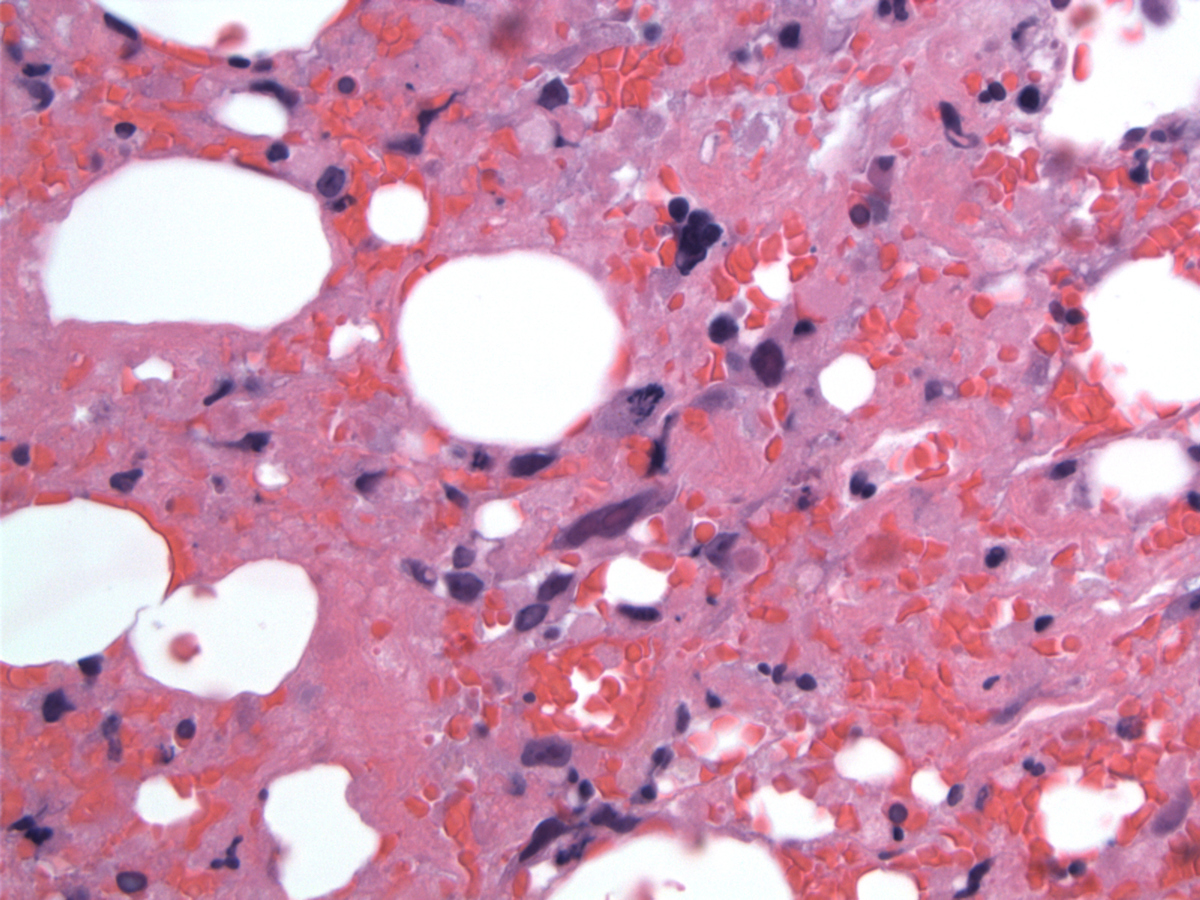

The formalin-fixed, paraffin-embedded biopsy showed hypocellular marrow with markedly decreased granulocytic and erythroid precursors, dyspoietic megakaryocytes, extensive stromal injury and rare interstitial atypical cells, medium to large size, with ovoid nuclei variably condensed chromatin, occasional prominent large eosinophilic central nucleoli and abundant cytoplasm. Rare Reed-Sternberg–like cell were seen but no lymphoid aggregate or fibrosis was identified. In the touch imprints the atypical cells have large or medium-sized hyperchromatic nuclei and large central nucleoli, abundant basophilic cytoplasm with eosinophilic granules. Peripheral blood shows pancytopenia with severe neutropenia, rare Döhle bodies and no circulating tumor cells.

| Stromal hemorrhage and fibrin and hyperchromatic megakaryocytes | ![]() |

| Large atypical lymphoma cells with abnormal mitoses | ![]() |

| Scattered lymphoma cells with cellular debris | ![]() |